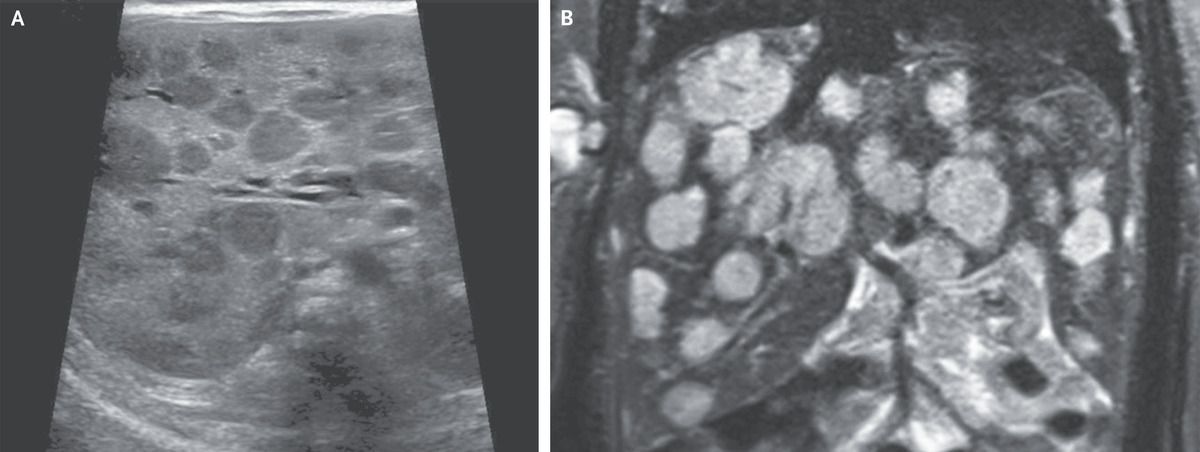

A 16-day-old girl who had not yet returned to her birth weight was brought to the emergency department with lethargy. She had tachypnea and marked hepatomegaly with a hepatic bruit, as well as eight small hemangiomas on the scalp, thorax, abdomen, and limbs that had been noted within days after birth. Abdominal ultrasonography showed numerous rounded hypoechoic lesions in the liver (Panel A). Whole-body magnetic resonance imaging showed contrast-enhancing hepatic lesions, as large as 20 mm in diameter, that were hyperintense on T2-weighted images (Panel B), a finding consistent with infantile hepatic hemangiomas. Moderate cardiomegaly was also noted. Laboratory studies showed a thyrotropin level of 25.5 mIU per liter (reference range, 0.50 to 8.50) and a reverse triiodothyronine level of greater than 3696 pmol per liter (reference range, 140 to 540). Complications of infantile hepatic hemangiomas include high-output cardiac failure, consumptive hypothyroidism, and bleeding. These vascular lesions typically have rapid growth followed by a phase of slow involution, sometimes over a period of years. Treatment with propranolol, furosemide, and high-dose levothyroxine was initiated. The liver lesions gradually reduced in size, and after 9 months, treatment was stopped successfully.